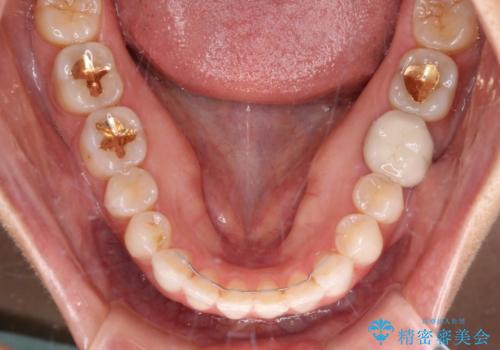

- 前歯のデコボコと上下スペースと前歯の隙間を気にして来院された患者様です。

目立たない装置を希望とのことでインビザラインにより、デコボコを解消しつつ、上下の前歯の隙間を閉じていくこととしました。

デコボコはあっという間に解消されましたが、上下前歯の隙間がなかなか解消されませんでした。

飲み込みの際に舌を前方に突出する癖があり、飲み込みの度に前歯に強く接触していたため、上下前歯の隙間が維持されていました。

舌の訓練を徹底していただいたことで、徐々に隙間は解消され、きれいな歯列に整えることができました。